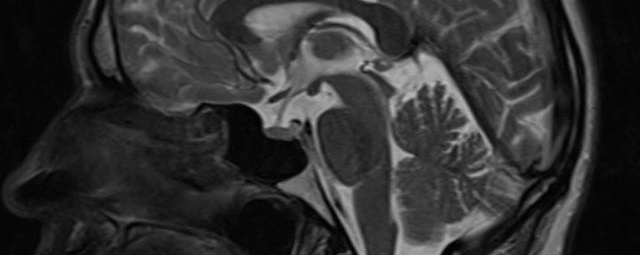

Kopf/Hals

• akute Schlaganfalldiagnostik und chronische Durchblutungsstörungen

• entzündliche Prozesse des Gehirns oder der Gesichtsweichteile

• Tumore

• Abklärung Schwindel, zentrale Sehstörung, Kopfschmerz

• Metastasenverdacht

• Multiple Sklerose

• Abklärung Hirnnerven, Schädelbasis inkl. Hypophyse

• Abklärung Kleinhirn, Hirnstamm, Halsmark

• intrakranielle Gefäße (Abklärung Verschluss, Stenose, Aneurysma)

• Halsgefäße zur Therapieplanung (z.B. Stent, Operation)